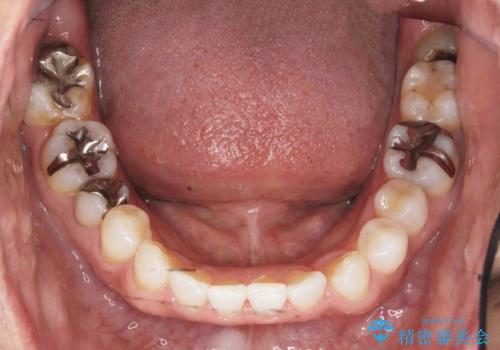

銀歯だらけの口の中を改善したい

- 口をあけた時に目立つ銀歯を白くしたい、と来院されました。

治療する部位や銀歯の下に虫歯が再発していたかどうか、神経処置の有無等の条件によりセラミックインレー・クラウンにするかを判断し長期的に虫歯が再発しにくいような口腔内環境を目指します。

見た目の改善だけではなく、長期的に虫歯の再発を防ぎ自分の歯を守るために銀歯をはずし、セラミック修復物・補綴物による機能回復を行いました。